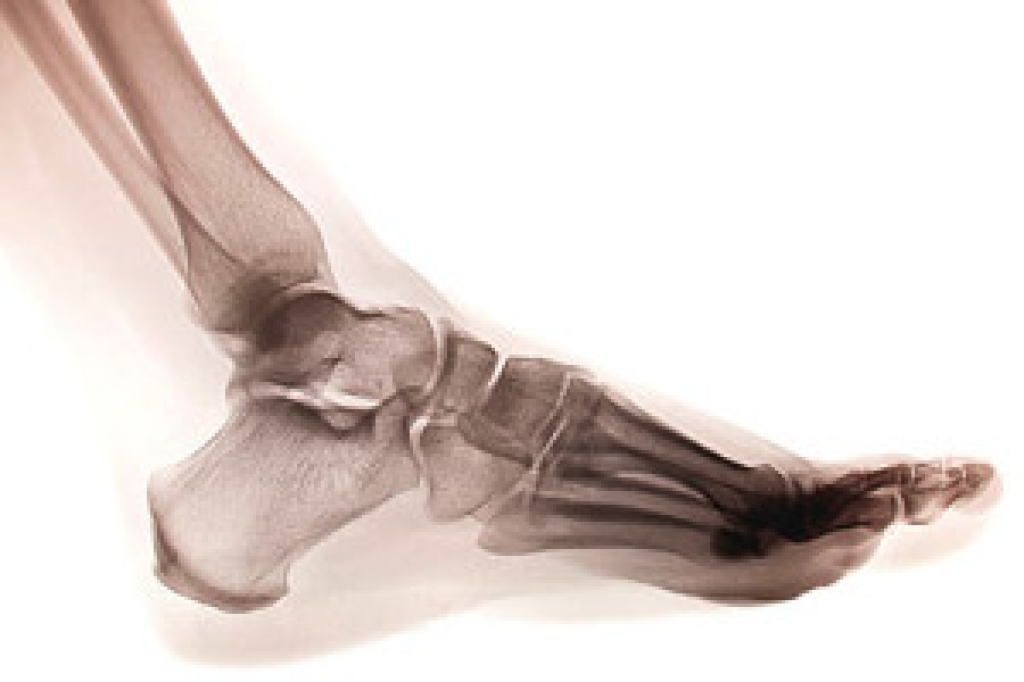

Dealing with Stress Fractures of the Foot and Ankle

Stress fractures occur in the foot and ankle when muscles in these areas weaken from too much or too little use. The feet and ankles then lose support when walking or running from the impact of the ground. Since there is no protection, the bones receive the full impact of each step. Stress on the feet can cause cracks to form in the bones, thus creating stress fractures.

What Are Stress Fractures?

Stress fractures occur frequently in individuals whose daily activities cause great impact on the feet and ankles. Stress factors are most common among: